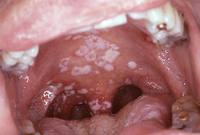

HIV in adults

Oral candidiasis in a patient with HIV